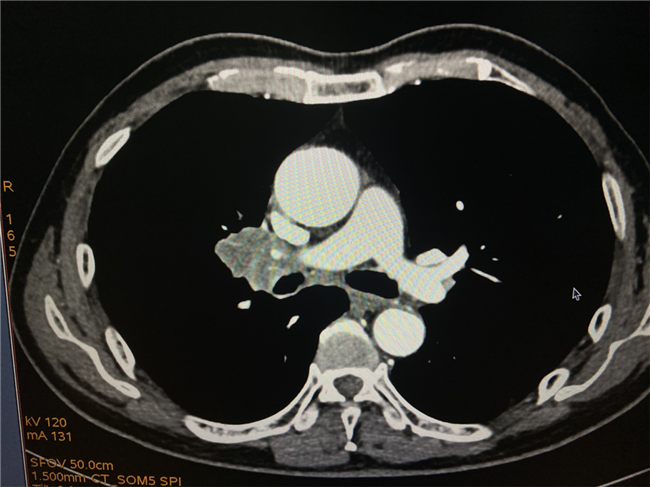

该名78岁的男性患者于2019年3月确诊为鳞状细胞肺癌,经支气管动脉灌注化疗曾一度病情缓解,但近期复查胸部CT示肿瘤病灶较前增大,考虑患者患者年龄较大,化疗效果不佳,常规放射治疗又难以耐受,为防止肿瘤进一步转移恶化,经与上级医院联合会诊后,呼吸内科团队决定对患者实施碘125放射性粒子植入治疗。

实施碘125放射性粒子植入治疗需要在CT引导下经皮肺穿刺,由于该患者的病灶在肺门部,进针的深度大,而且临近腔静脉,为减少对患者的创伤,需要快速精准的到达病灶部位,大大增加了进针的难度。4月12日,在南昌大学第一附属医院教授指导下,呼吸科和影像科紧密协作,经多番讨论后决定采取“多针多排进针”的方案。在短短1小时内成功为患者植入28颗碘粒子。

放射性粒子治疗肿瘤是一种安全有效的精准微创治疗方式。在CT引导下,精确植入碘125粒子至病灶内,是将低能量的γ射线的碘125粒子植入组织内,对肿瘤组织进行持续性、最大程度的毁灭性杀伤。该项技术对局部治疗可达到或接近其他毁损病灶疗法的效果,具有创伤小、安全性高、可重复等特点,是微创介入治疗的一种新型治疗方式。其显著优势包括:内照射射线剂量小,作用时间更长,治疗定位更准确,对肿瘤局部作用均匀,辐射半径小(两厘米左右),对周围正常组织损伤极小,是一种非常好的局部治疗措施。